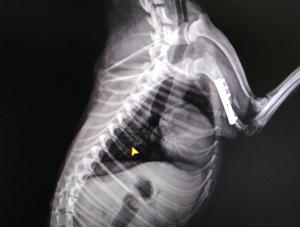

康复案例

其他宠物

洛阳宠物医院1

洛阳宠物医院2

洛阳宠物医院3